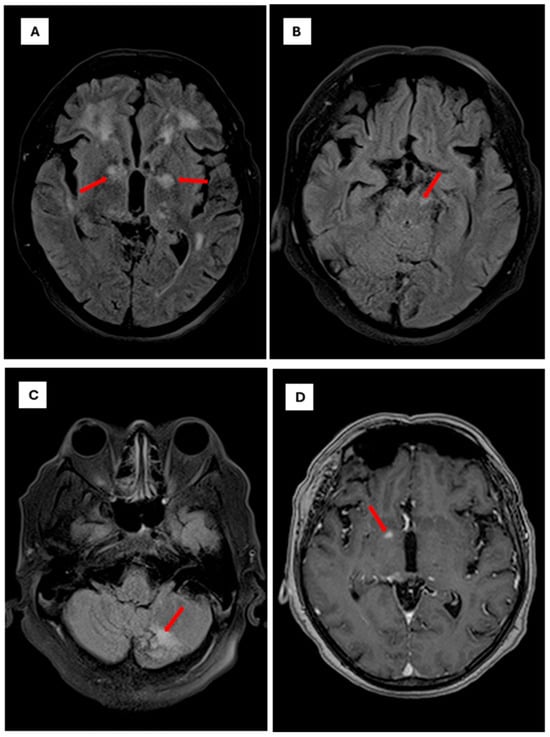

Central nervous system (CNS) cryptococcosis caused by Cryptococcus neoformans is a severe opportunistic infection that primarily affects individuals with impaired cellular immunity. Although the classic presentation includes headache, fever, and meningeal signs, chronically immunosuppressed patients may develop atypical neuropsychiatric manifestations, leading to diagnostic delays. We report the case of a 53-year-old man with rheumatoid arthritis (RA) receiving long-term prednisolone and etanercept therapy, who presented with a 7-day history of depressive mood, anhedonia, social withdrawal, irritability, and progressive confusion. Neurological examination revealed disorientation without focal deficits. Brain imaging showed only mild cortical atrophy, and cerebrospinal fluid (CSF) analysis revealed lymphocytic pleocytosis, low glucose, and elevated protein levels. Multiplex PCR (FilmArray®) of CSF identified Cryptococcus neoformans, CSF positive to C. neoformans. The patient was treated with liposomal amphotericin B followed by fluconazole, resulting in gradual improvement of both neurological and psychiatric symptoms. This case highlights an unusual presentation of CNS cryptococcosis in a non-HIV immunosuppressed patient with RA, emphasizing that acute psychiatric or cognitive changes can be the predominant manifestation. Clinicians should consider fungal infections in the differential diagnosis of acute neuropsychiatric symptoms in patients receiving chronic corticosteroid and biologic therapy. Early recognition and molecular diagnosis can facilitate timely antifungal treatment, potentially improving prognosis and reducing morbidity associated with delayed therapy. This report underscores the importance of awareness of atypical presentations of opportunistic infections in immunosuppressed populations. Full article

Figure 1